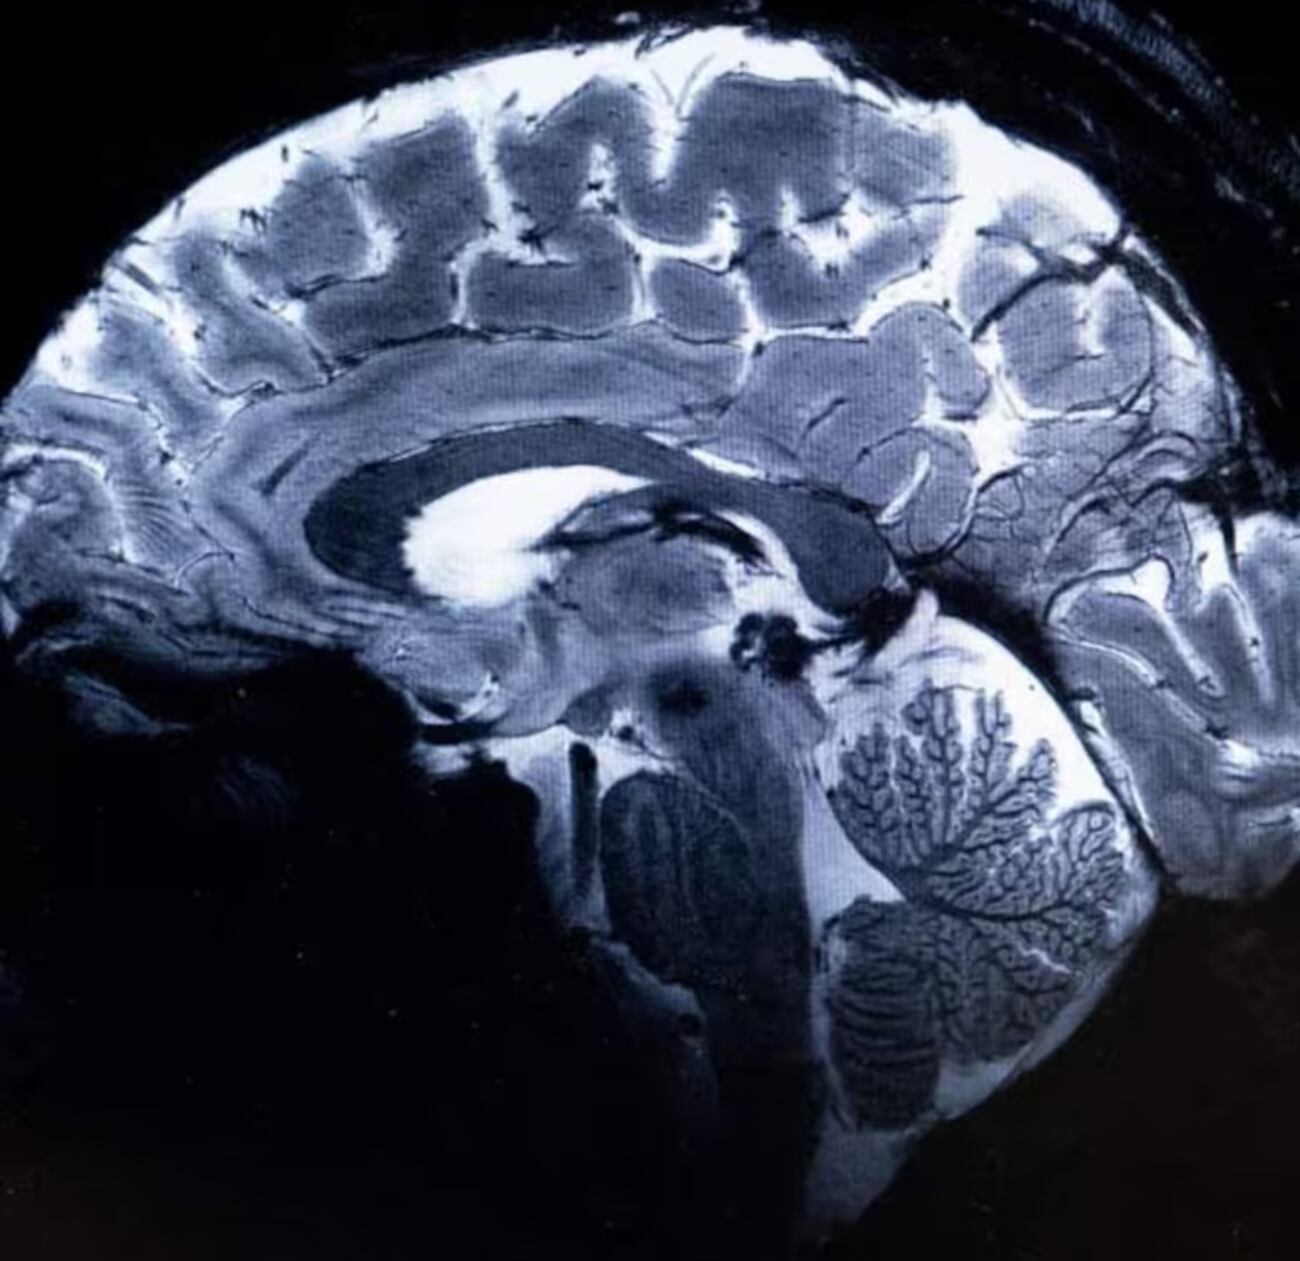

Un grupo de investigadores del Comisariado de Energía Atómica (CEA) escanearon el cerebro de 20 personas voluntarias. Los expertos decidieron comparar los resultados de la maquina, llamada Iseult, con otro escáner normal. El primero puede digitalizar diez veces más ya que cuenta con un campo magnético de 11,7 teslas, a diferencia del segundo que no pasa los tres teslas.

“Hemos visto un nivel de precisión nunca antes alcanzado en el CEA. Con esta máquina podemos ver los pequeños vasos que alimentan la corteza cerebral, o detalles del cerebelo que eran casi invisibles hasta ahora”, dijo Alexandre Vignaud, integrante del estudio científico.

Asimismo, se espera que esta potente maquina ayude en los artilugios que se enconden detrás de las enfermedades, ya sea el Parkinson o el Alzheimer, y también problemas psicológicos como depresión o esquizofrenia. Por ello, los especialistas tratan de encontrar cómo los medicamentos utilizados con la finalidad de tratar diferentes trastornos se esparcen mediante el cerebro.

“Por ejemplo, sabemos que una área particular del cerebro, el hipocampo, está implicada en la enfermedad del Alzheimer, por lo que esperamos poder descubrir cómo funcionan las células en esta parte de la corteza cerebral”, sostuvo la investigadora Anne-Isabelle Etienvre. Como se sabe, este logro se debe a 20 años de muchas investigaciones entre franceses y alemanes, aunque ellos no son los únicos por ahora, pues Estados Unidos y Corea del Sur trabajan en una de estas maquinas sin poder registrar aún a personas.